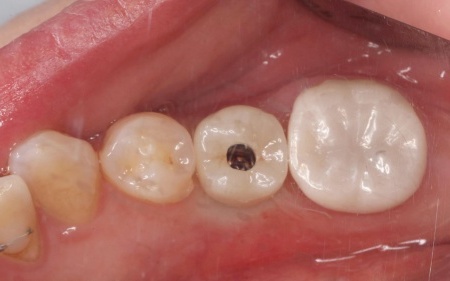

| 行ったご提案・治療内容 | 診断結果をお伝えし、患者様の了承を得たうえで左下奥歯の被せ物を外したところ、レントゲン検査での診断どおり、歯根が割れていることが確認できました。 そのため、患者様には左上下奥歯とも温存が難しい旨を説明し、抜歯に同意いただきました。 患者様は、以前当院で人工歯根を顎の骨に埋入して歯を装着するインプラント治療を受けていたため、今回も左上下奥歯ともインプラント治療を希望されています。 メリット デメリット 改めてメリットとデメリットをしっかりお伝えしたところ、インプラント治療に対する不安はないとのことで、治療に同意いただきました。 まず、左上下奥歯を慎重に抜きます。 インプラント手術後は経過観察を行い、インプラントが顎の骨に結合したことを確認したら、インプラント上部に取り付ける人工歯を作製するために精密な型取りを実施します。 後日、完成した人工歯をインプラントに装着し、使用感や見た目に問題がないことを確認して、治療を終了しました。 |

治療後